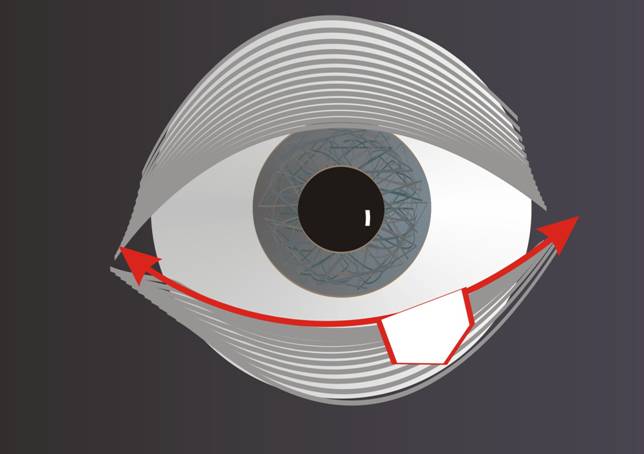

Fig. 1: Un defecto del párpado inferior hasta un tercio se puede cerrar por transposición de los restos del párpado. |

Las incisiones, necesarias en el margen palpebral para eliminar el tumor, tienen que efectuarse en el mismo ángulo para poder reunir los restos del párpado y formar una línea recta del nuevo margen. Los defectos de hasta un tercio se pueden cerrar por transposición de los dos tercios restantes del párpado. Los defectos algo más grandes se pueden cerrar si hay bastante laxitud o si se desconecta el resto del párpado lateral del margen orbitario, esto se consigue con una sección del tendón palpebral lateral en el ángulo lateral (cantolísis lateral).